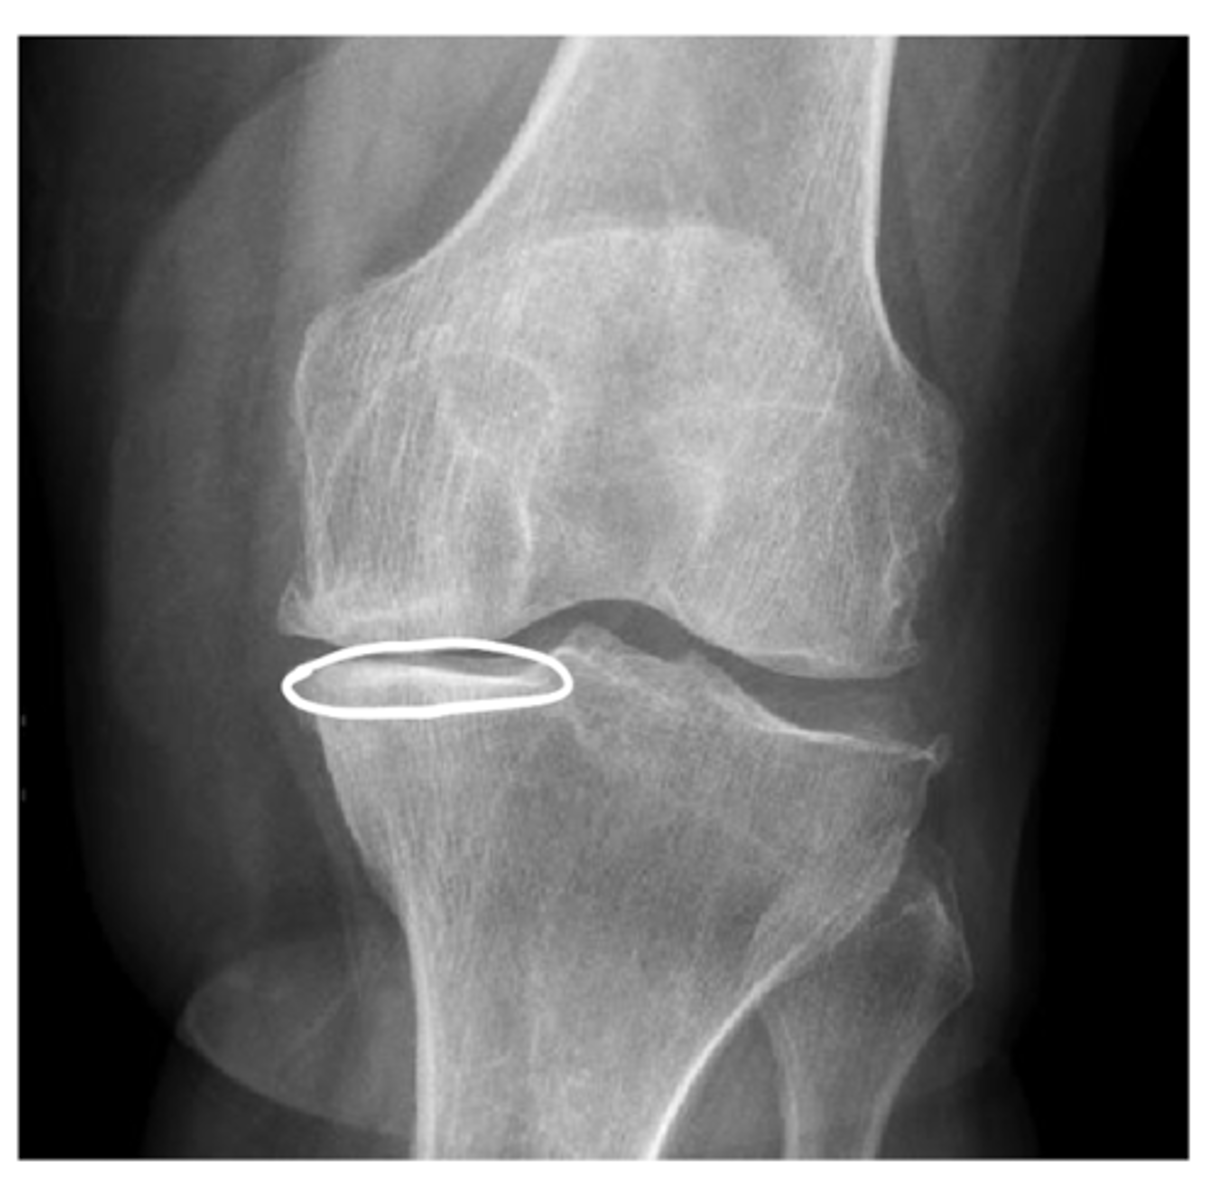

List the 3x components of (C) cartilage space when interpreting plain film radiographs

1. "space" can be an indirect assessment of radiolucent cartilage

2. Subchondral bone -- sclerosis vs. erosions

If we identify a loss of joint space on a plain film radiograph, what may this imply?

Loss of cartilage (primary indication of OA, along with bone spurs and sclerosis)

What are erosions? What do they indicate?

Scalloped, notched edges that indicate cartilage damage and wearing away of bone -- think rheumatic diseases (RA, PA, etc.)

1. Muscles - atrophy - swelling (ex: swelling around the knee joint as seen in this image)